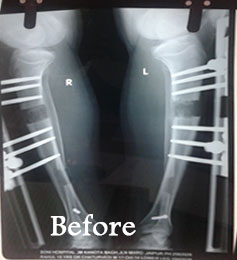

Limb lengthening